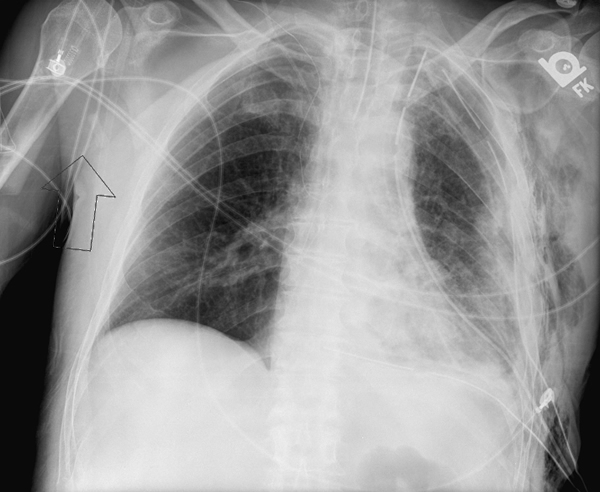

Туберкулезная эмпиема на латинском - фото презентация